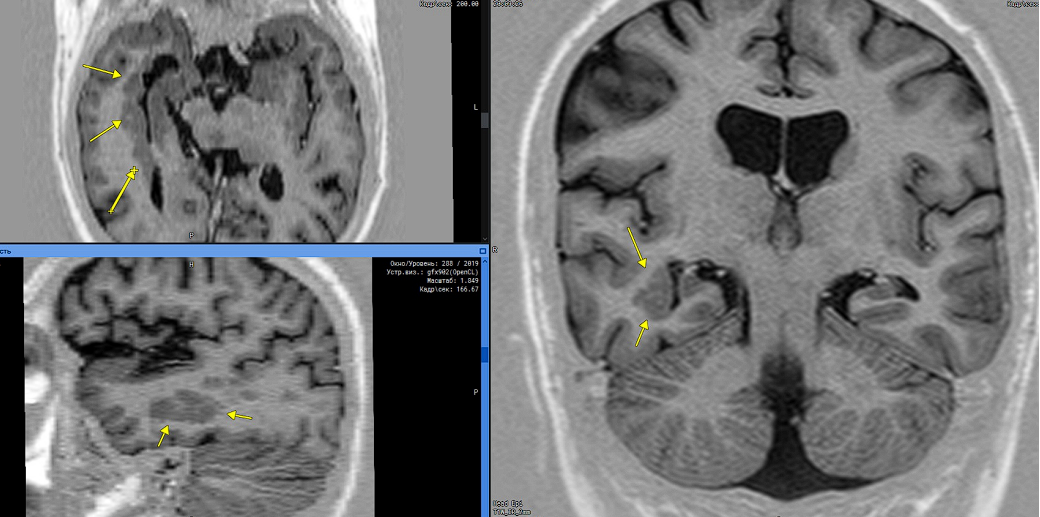

Рассмотрим клинический пример:

Женщина, 20 лет, с жалобами на впервые возникший эпиприступ.

1️. Перивентрикулярно, субэпендимально в области заднего и височного рогов правого бокового желудочка определяются множественные участки серого вещества (характеристики МР-сигнала идентичны серому веществу головного мозга) округлой формы с четкими контурами, без перифокальной реакции, протяженностью в переднезаднем направлении 5.9 см, шириной до 1.0 см, и кранио-каудальным размером до 1.5 см. /Рис 1/.

Рис 1. Желтыми стрелками указаны участки перивентрикулярной гетеротопии серого вещества.

2️. Нижние и задние отделы червя мозжечка гипоплазированы. Отверстие Можанди и полость IV-го желудочка расширены. IV-ый желудочек и большая цистерна мозга широко соединяются. Большая цистерна мозга, понто-медуллярная, передняя цистерна моста мозга и межножковые цистерны расширены. Намет мозжечка располагается обычно. /Рис 2/

Рис 2. Желтыми стрелками указано широкое сообщение полости III-го желудочка с большой цистерной, а также гипоплазия мозжечка.

3️. Боковые желудочки мозга симметричны, умеренно расширены, , индекс тел боковых желудочков - 33 (норма до 18-22) ВКИ 1 - 23.7 /норма 24,0-26,3, после 60 лет до 30,0/; без перивентрикулярной инфильтрации. III-й желудочек расширен - 1.3 см (норма у детей до 0,5 см, до 60 лет – 0,7 см, после 60 лет 0,9 см). IV-й желудочек расширен, ВКИ - 20 /норма 11,3-13,0/.  /Рис 3,4/.

Рис 3. Желтыми стрелками указано расширение боковых желудочков.

Рис 4. Желтыми стрелками показано расширение III-го желудочка.